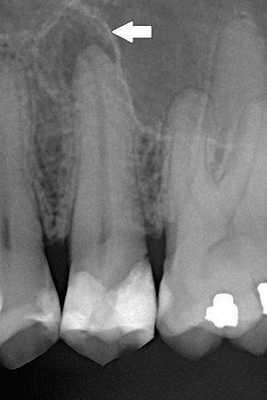

Диагностика периодонтита проводится на основании жалоб пациента, анамнеза заболевания, оценки общесоматического статуса, осмотра головы и шеи, полости рта, зуба, его перкуссии, зондирования и термопробы, электроодонтодиагностики (ЭОМ) и рентгенологического исследования. [10]

Чаще всего клиническая картина соответствует острому периодонтиту, за исключением того, что всегда рентгенологически выявляются изменения в тканях периодонта, характерные для той или иной формы периодонтита. [12]